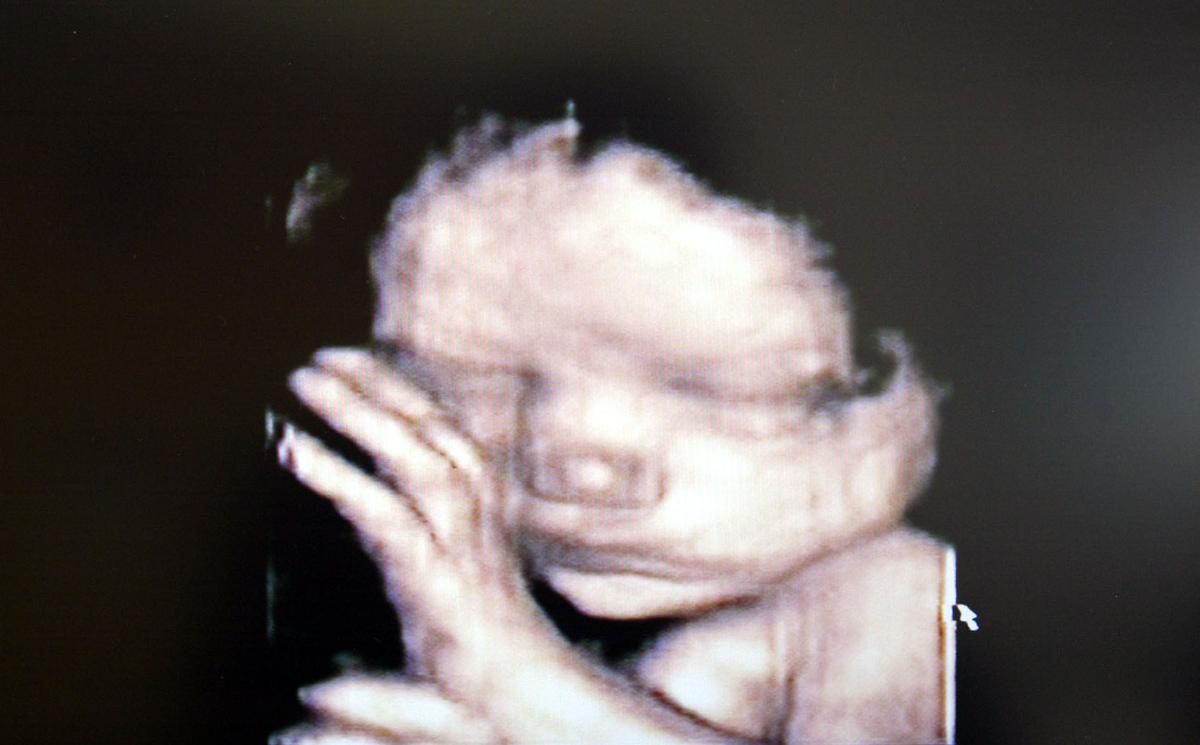

Two state legislators have released a draft bill that would make abortion murder in the state of Idaho.

Republican Rep. Heather Scott (R-Blanchard), who was joined by fellow Rep. John Green (R-Post Falls), released the draft of their “Idaho Abortion Human Rights Act” on Jan. 22.